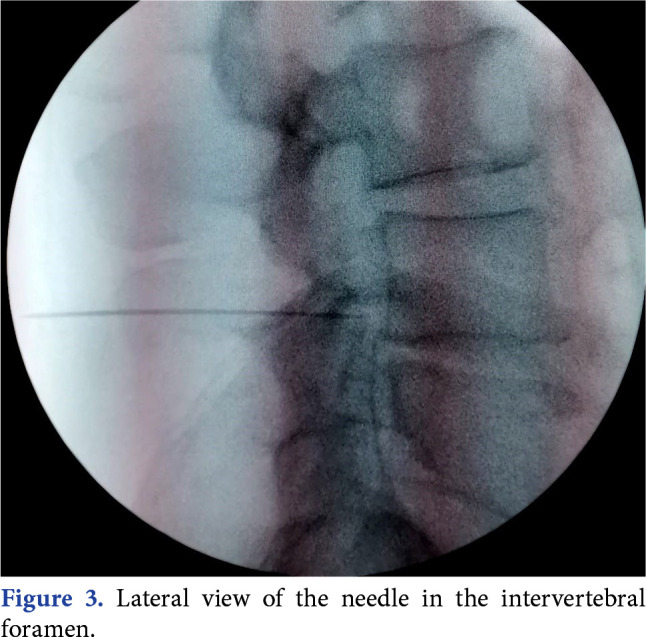

Objectives: This study aimed to compare the treatment outcomes between dorsal root ganglion (DRG) pulsed radiofrequency (PRF) and DRG PRF plus transforaminal epidural steroid injection (TFESI) in patients with chronic lumbosacral radicular pain.

Patients and methods: Eighty-one patients (39 males, 42 females; mean age: 57.5±11.9 years; range 18 to 65 years) who underwent DRG PRF (Group 1) and 59 patients (34 males, 25 females; mean age: 58.7±12.3 years; range 18 to 65 years) who underwent DRG PRF plus TFESI (Group 2) between February 2021 and June 2022 were enrolled in the retrospective study. A Visual Analog Scale (VAS) was used to assess pain severity. Patients in both groups were evaluated before treatment and at four weeks and six months after treatment.